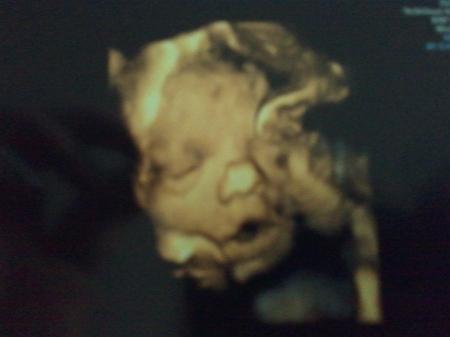

Ich bin so glücklich nur noch am heulen meine Hormone spielen verrückt :D aber er ist so süß *-* ich kanns nicht mehr abwarten :D also ich bin jetzt 29 +6 und der "kleine" ist jetzt 42 cm groß & 1590 gramm "leicht" :D ist das bei euch ähnlich ? würd mich mal interessieren :p Ps. Qulität ist jetzt nicht so der hammer :p

meine kleine schmollbacke :D